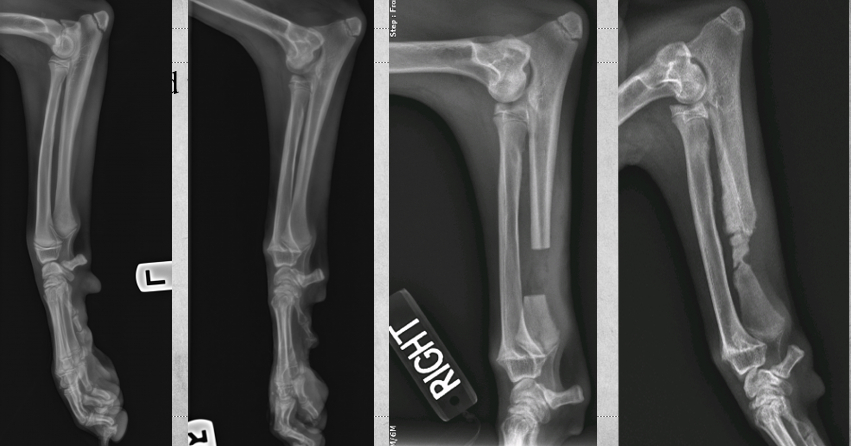

identify left to right

left to right:

Transverse fracture

Oblique fracture

Spiral fracture